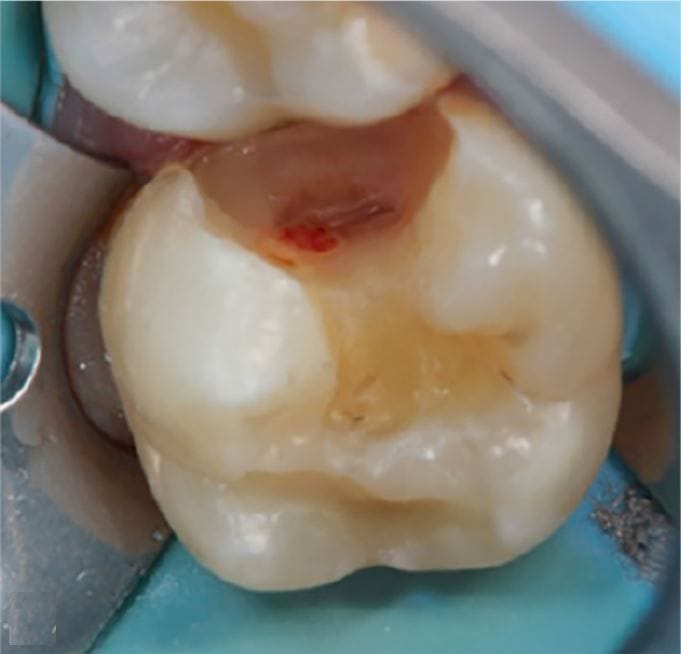

Behandeling van pijnklachten komt regelmatig voor. Niet altijd wordt daar voldoende tijd voor uitgetrokken, waardoor de pijn kan voortduren. Jan Warnsinck bespreekt de hoofdoorzaken van tand- en kiespijn en de behandeling.